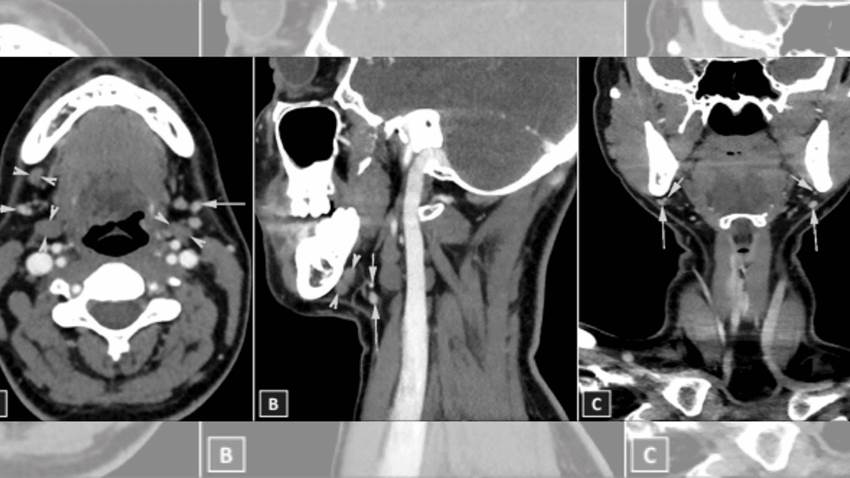

Describen raro caso de aplasia bilateral de la glándula submandibular

La aplasia se ha definido como el desarrollo defectuoso o ausencia congénita de tejido o de un órgano, mientras que las glándulas submandibulares son...